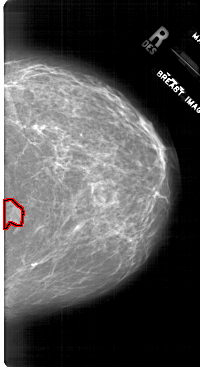

A_1745_1.LEFT_MLO

LEFT_MLO LINES 6526 PIXELS_PER_LINE 4051 BITS_PER_PIXEL 12 RESOLUTION 43.5 NON_OVERLAY

FILE: A_1745_1.RIGHT_MLO.OVERLAY

TOTAL_ABNORMALITIES 1

ABNORMALITY 1

LESION_TYPE MASS SHAPE IRREGULAR MARGINS ILL_DEFINED

ASSESSMENT 4

SUBTLETY 2

PATHOLOGY BENIGN

TOTAL_OUTLINES 1

BOUNDARY